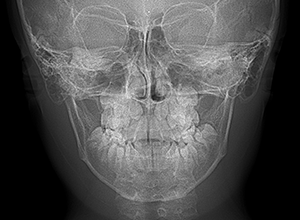

| セファロ所見 | Sellaに対して下顎頭は後方位だが下顎骨は大きくしっかりとした形態をしており前後的にはⅠ級、垂直的にはロウアングルの骨格形態をしていた。 上顎前歯は唇側傾斜を呈していた。 |